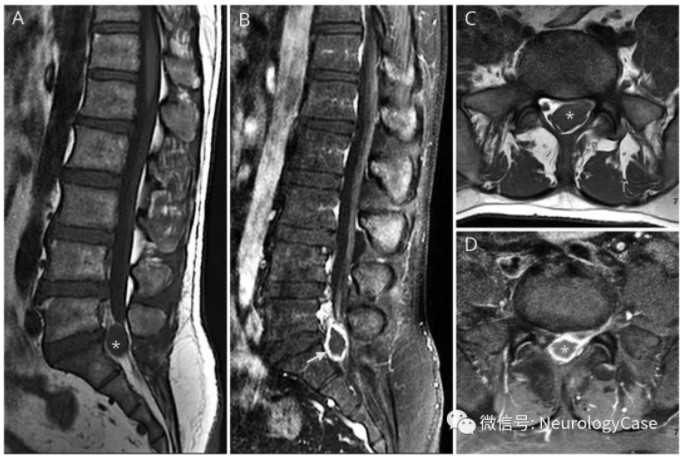

47岁健康男性,表现为间歇性下背痛放射至左侧小腿;1个月内,夜间疼痛加重,影响睡眠。查体提示左外侧小腿感觉异常,左脚踝跖屈无力,踝反射减退。神经影像学可见L5-S1水平2×1.2cm结节几乎完全闭塞椎管,钆增强MRI上呈环形强化(图1)

图1 腰椎矢状位T1平扫[A]和钆增强(B)MRI可见L5-S1水平一2×1.2 cm结节伴环形强化(箭头),压迫硬膜囊;L5-S1水平的轴位T1平扫[C]和增强[D]MRI可见结节几乎完全闭塞椎管